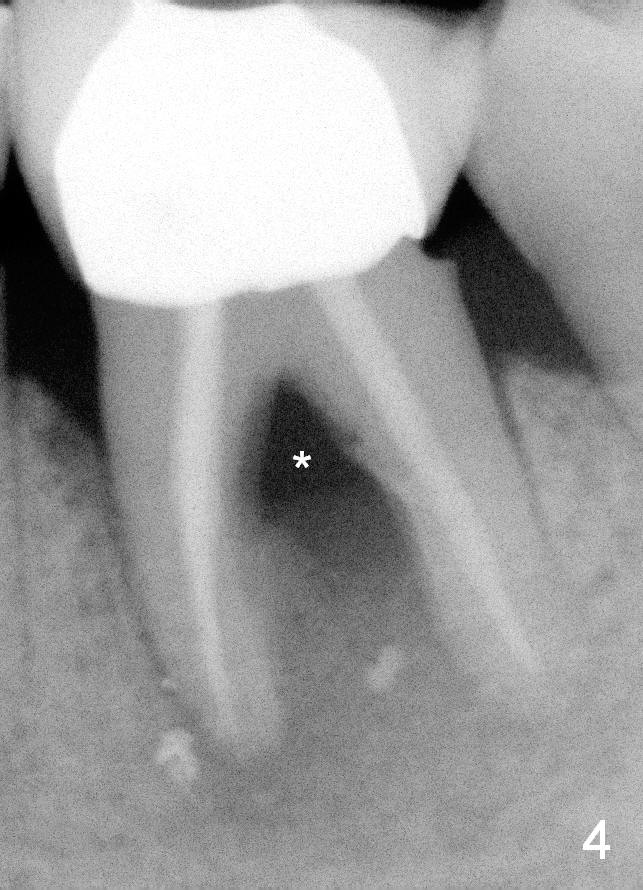

A 59-year-old lady has history of periodontal disease and bruxism. The tooth #19 has pulpitis after unsuccessful DO composite (Fig.1 *) and requires root canal therapy (Fig.2). Six months later, a fistula is found to communicate with the furca (Fig.3 *: gutta percha). Less than 3 years, the furca enlarges with symptoms of infection (Fig.4 *). She works out of state. The Principle of No Implant, No Extraction is adhered. Since she is of short statue, the bone height is relatively limited. A 6x14 mm tissue-level implant is appropriate (Fig.5, one piece). Sensor 1 may be proper for her small mouth. When the bottom of the socket is large and close to the Inferior Alveolar Nerve, can an immediate implant be placed?